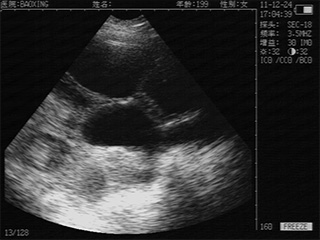

优质图像